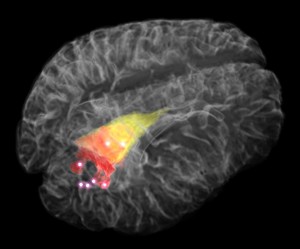

The hand-held device, called a Raman spectroscopy probe, was developed by researchers at McGill University for use by neurosurgeons in the removal of brain tumours called gliomas, which typically infiltrate healthy brain tissue.

The difficulty for surgeons is that current imaging technologies like MRI are unable to detect all the malignant cells that have seeded themselves within normal tissue outside the solid tumour, said Dr. Kevin Petrecca, the chief of neurosurgery at the Montreal Neurological Institute who helped design and test the probe.

By using Raman spectroscopy — a technique that measures the way an object’s molecules scatter light — Petrecca said neurosurgeons can pinpoint cancer cells in small spots about a millimetre deep where the probe comes in contact with brain tissue.

In a study published Wednesday in Science Translational Medicine, the researchers showed the device detected not only the dense tumour mass, but also individual cancer cells that had penetrated surrounding tissue in 17 patients with advanced gliomas.